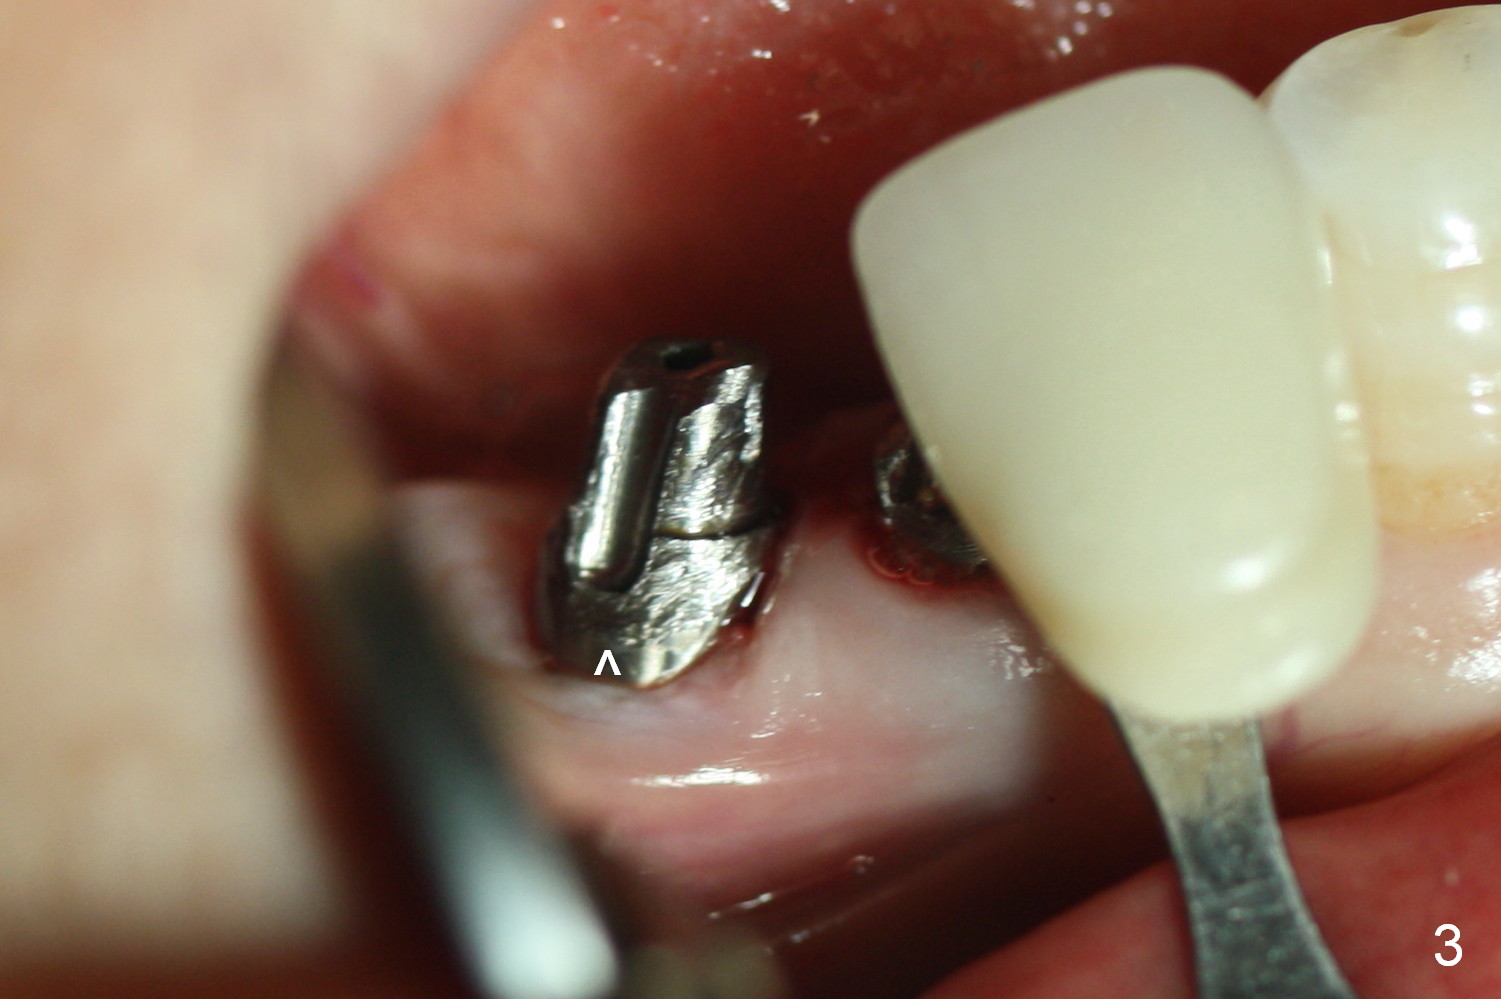

Four months and a half, the buccal margin has to be extended (Fig.3 ^). A month later, gingival recession becomes more obvious (Fig.4 ^ with exposure of the rough surface of the implant). Occlusal view demonstrates the buccal position of the implant and abutment at #29 (Fig.5). CBCT will be taken to confirm the malpositioning. If it is confirmed, the abutment and implant will be removed and un-torqued. The lingual bone will be removed; osteotomy will be also extended apically cautiously. The same or longer implant will be placed immediately. Probably two 1 piece implants will be placed at the same time at the site of #30, since the ridge is narrow.